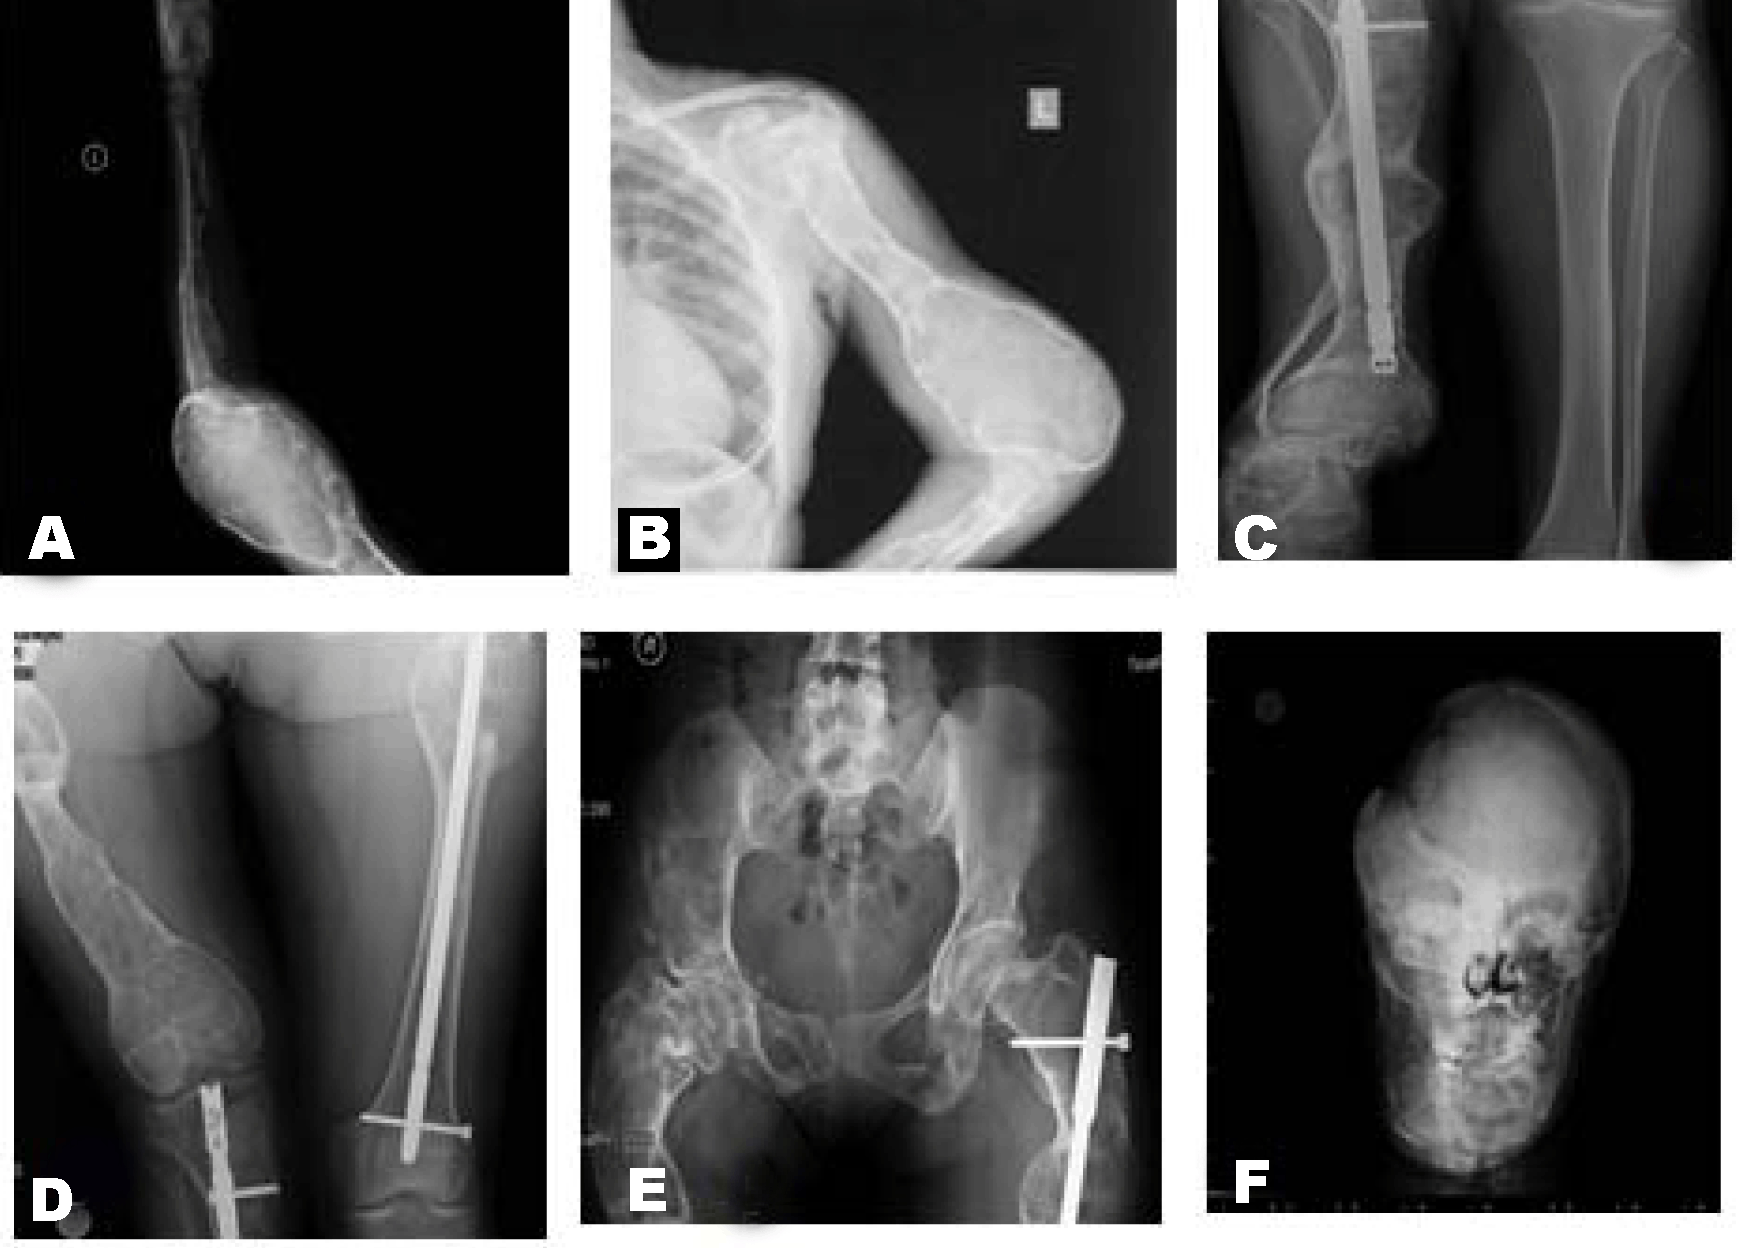

A 21-year-old female was referred to our hospital with the facial deformities. She had pathological fracture of right femur when she was two years old. Histopathological diagnosis was fibrous dysplasia. Recurrent fractures had occured at left arm and left hip (Figure 1A-E). There were intramedullary nails at right tibia and left femur (Figure 1C-E). The deformities of extremities were shown in Figure 1A-E. There was a scene of expansion of distal humerus related to cystic change of bone (Figure 1A-B). In Figure 1C-D, there were severe bowing deformity of long bones, tibia and femur, respecitvely. There was shortening of bones of tibia, fibula and femur. Fibula was hypoplastic (Figure 1C). Lytic lesion at the iliac bone was seen in Figure 1E. There were deformities of mandible and other craniofacial region. Heterogenous sclerotic changes of the calvarial bones related to fibrous dysplasia was occured in Figure 1F. There was no aeration in right maxillary and frontal sinuses. There was predominant expansion and sclerotic changes of right orbita (Figure 1F). She had underwent operations beacause of the compression of cranial nerves and facial deformity. Besides, pamidronate was administered intravenously (consecutive 3 days, total 180 mg) as medical therapy. The patient had recovered from her symptoms with bisphosphanate treatment. Improvement in bone turnover markers was observed with treatment but there was no change in radiographic appearance.

Figure 1: X-ray of long bones and calvarium. (A) Lateral view of left humerus, (B) Anterior view of left humerus, (C) View of intramedullary nail at tibia, (D) View of intra medullary nail at femur, (E) Anterior view of pelvis, and (F) Anterior view of the head.